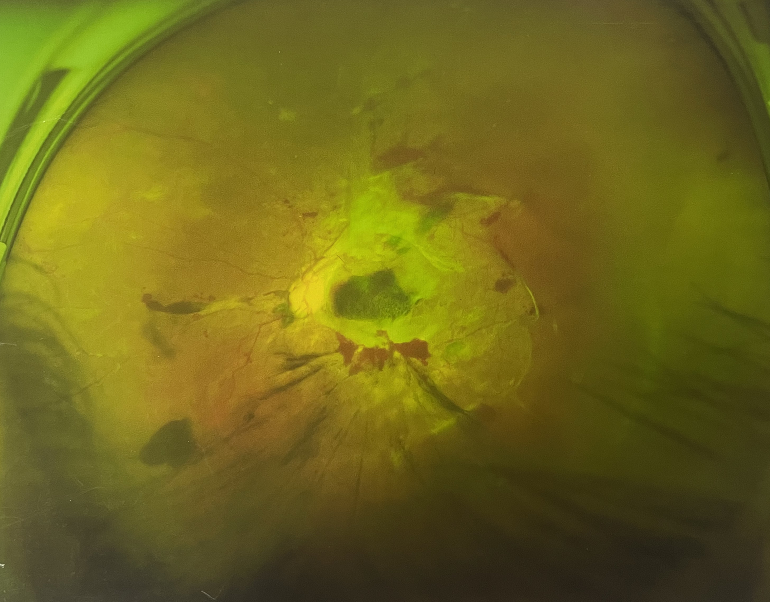

眼底出血一般多久能好?眼底出血可以由眼科本身疾病引起,常見的是視網(wǎng)膜靜脈阻塞、糖尿病視網(wǎng)膜病變、中心性滲出性視網(wǎng)膜病變、視網(wǎng)膜動(dòng)脈硬化、老年性黃斑病變、視網(wǎng)膜靜脈周圍炎。

另外,眼底出血還可以由全身疾病引起,比如糖尿病可以引起眼底出血,高血壓也會(huì)引起眼底出血,還有嚴(yán)重的腎病,血液方面的疾病都可以導(dǎo)致眼底出血。

眼底出血一般多久能好?眼底出血如果是輕癥,時(shí)間較短的患者大約3-6個(gè)月可以恢復(fù),如果是重癥或者病程較長的患者,可能要持續(xù)1年,甚至2年時(shí)間。

眼底出血一般多久能好?眼底出血是醫(yī)生用檢眼鏡才能看到,患者和其他人看不見。眼底出血不是單獨(dú)的病,一般來說是由眼科本身疾病造成,還可以由全身疾病造成。比如常見的視網(wǎng)膜靜脈阻塞、糖尿病視網(wǎng)膜病變等引起的眼底出血較常見。眼底出血一般多久能好?所以眼底出血的出血吸收時(shí)間也不一樣,要根據(jù)病情輕重決定其預(yù)后,出血吸收時(shí)間也不一樣。